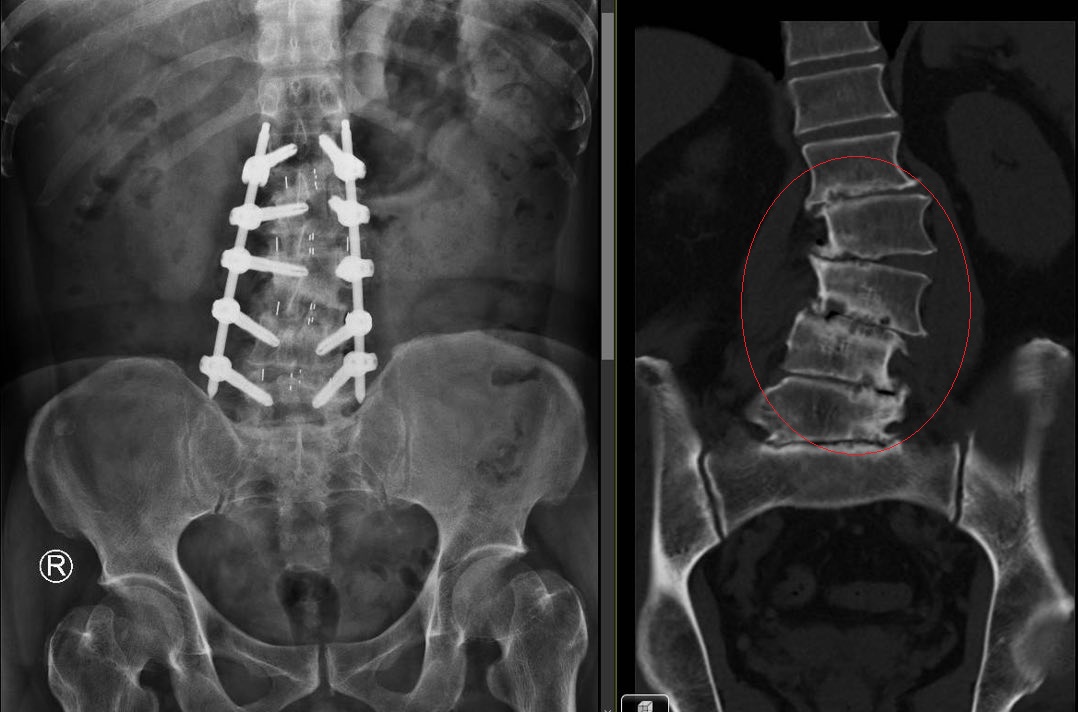

北榮手外科王榮磻主任表示,由於有些臂叢神經損傷無法自行恢復,因此及早正確的診斷評估非常重要,包括透過理學神經學檢查評估肩部上肢手部的肌肉力量和感覺異常的分布情形,以及精密的影像學檢查(如磁振造影檢查)來幫助定位臂叢神經損傷病灶。除此之外,神經傳導檢查/肌電圖檢查是手外科醫師確診臂叢神經損傷之最佳利器;通常會在臂叢神經損傷後6週進行第一次的神經傳導檢查/肌電圖檢查,之後在臂叢神經損傷後2~3個月進行第二次的神經傳導檢查/肌電圖檢查,藉此觀察比較臂叢神經損傷的恢復變化。

針對成人之臂叢神經損傷之顯微重建治療,王榮磻指出,近年來由於對臂叢神經之解剖位置認知、影像醫學技術之革新、神經接合之材料科技進步,使得臂叢神經損傷之手術治療有了長足之轉變。目前急性臂叢神經損傷之手術治療趨勢是神經轉位手術,相較於傳統神經移植修補手術能有更短的住院天數(轉位手術術後僅需2~3天觀察,移植修補手術術後往往需一週觀察)及更少的活動限制(轉位手術術後僅需手臂吊帶保護和避免過肩姿勢,移植修補手術則需要肩頸部活動限制避免移植處拉扯)、術後恢復時間也有較快進展。而若是慢性臂叢神經叢損傷之肩部與手肘失能之手術治療,除了傳統肌腱轉位手術之外,透過游離功能性顯微肌瓣轉位手術亦是重建上肢功能的方式。